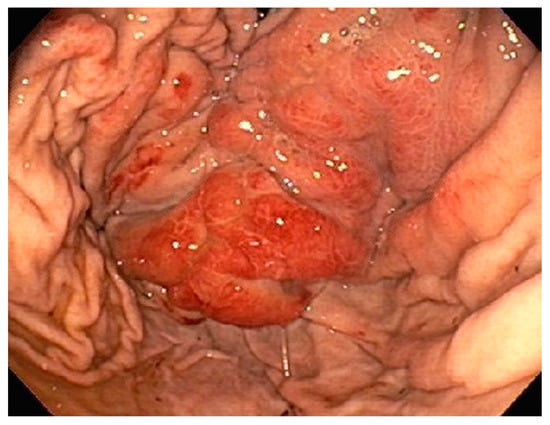

| 1 | F | 66 | Skin | Fundus, cardia, and body | Polypoid lesions with superficial ulcers | Esophagus, duodenum, mediastinum, cervical soft tissue, pancreas | Metastatic malignant melanoma | Radiotherapy and immunotherapy | Comfort care and death 5 days after EGD diagnosis of metastasis |

| 4 | F | 73 | Kidney | Fundus and body | Multiple large friable masses | Liver and lungs | Clear cell renal carcinoma | Nephrectomy, chemotherapy, immunotherapy (Axitinib) | Death 10 days after EGD diagnosis of metastasis |